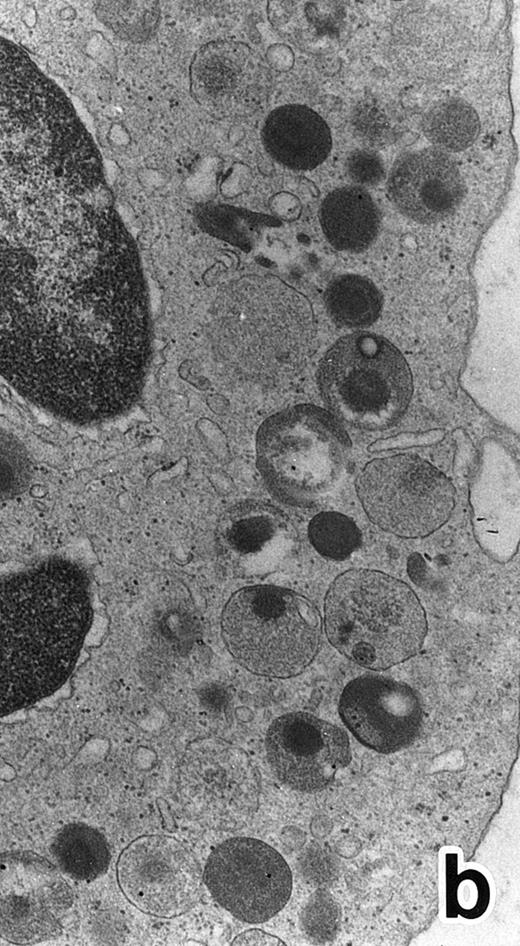

(a) A PMN in patient no. 2 after 10 days of ATRA treatment. The nuclei are irregularly lobulated, with some of them being connected by nuclear filamentous structures, and heterochromatin is condensed along the nuclear membrane. (Original magnification × 13,100.) (b) Higher magnification of a portion of the cell in (a). The cytoplasmic granules are large and spherical, and some of them contain flocculent material and central cores with higher electron density. (Original magnification × 20,200.)

Common morphological changes of bone marrow leukemia cells were observed during ATRA treatment. After 1 week of ATRA treatment, leukemic cells showed heterochromatin condensation and nuclear lobulation (Figs 3 and 4). Although the lobulated nuclei of some cells resembled those of PMNs, these nuclei were irregular in shape and nucleoli were occasionally present. The lobulated nuclei often had nuclear blebs (Fig 3a) or were connected by thin nuclear material (Fig 4a), called filamentous connections,13 that consisted of heterochromatin delimited by the nuclear membrane. In addition to these changes, the irregularly shaped primary granules became morphologically normal. This was most evident in patient no. 1, in whom the majority of both Auer rods and irregularly shaped inclusions, as shown in Fig 2, dramatically vanished and the remaining primary granules appeared normal, being spherical in shape and relatively homogeneous in size (Fig 3a), although abnormal primary granules and/or Auer rods were infrequently observed in some cells. Rarely, a structure composed of an Auer rod coupled with a primary granule was found, appearing as though the seemingly normal primary granule had emerged from the Auer rod (Fig 3b). Type I primary granules still predominated in all patients, but type II primary granules with a nucleoid structure were rarely observed in patients no. 1 and 2. Some maturing neutrophils with abnormally shaped lobulated nuclei in patient no. 2 possessed unusual, possibly immature, primary granules containing central electron-dense material (Fig 4a and b), indicating asynchronous maturation of nuclei and cytoplasmic granules.